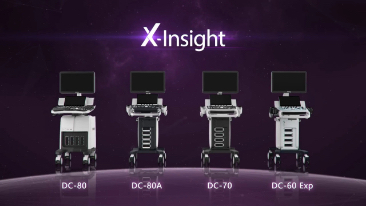

X-Insight

Overview

The best patient care is your ultimate goal. To achieve this requires confident diagnosis even with daily increases in patient throughput. Built on the foundation of MindrayŌĆÖs continuous customer insights into clinical needs and the inheritance from premium technology, the DC-80 with X-Insight is designed to help you manage your daily output with high efficiency, no matter what type patients and clinical challenges you will face.